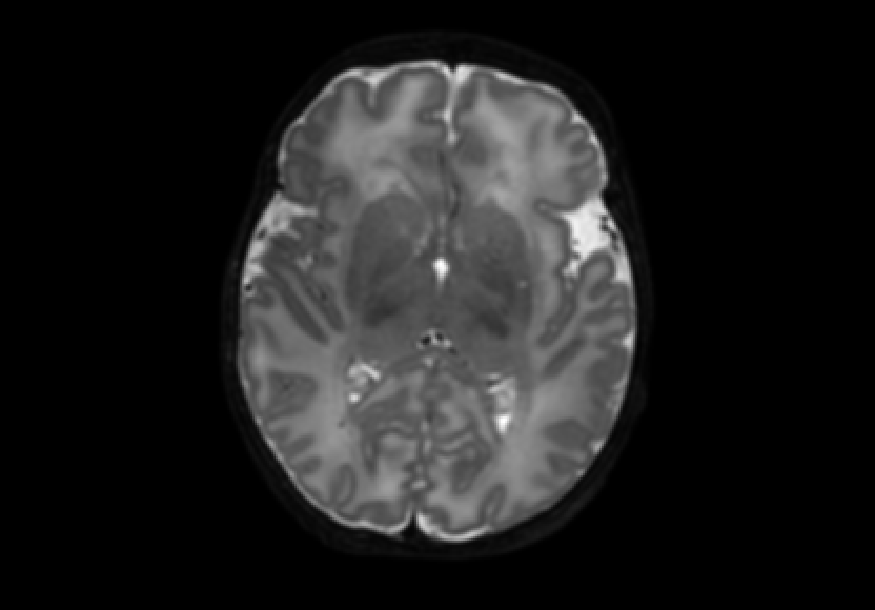

The dataset consisted of 70 3D T2-weighted brain MRI scans publicly available from the dHCP neonatal cohort. The segmentation maps had 10 classes, corresponding to: zero-pixel background, cerebrospinal fluid (CSF), cortical grey matter (cGM), white matter (WM), background bordering brain tissues, ventricles, cerebellum, deep grey matter (dGM), brainstem, and hippocampus. The scans covered an age range of 24.3-42.2 weeks. The data was available in NIfTI format; Figure 1 shows an example scan and corresponding tissue labels. We carried out a pre-processing step where each scan was independently normalised to zero-mean and unit-variance.

Blur is a rather unique family of MRI artefacts because it can be introduced into a scan after the acquisition stage, such as during post-processing or in the manifestation of pathological conditions [7]; simulating blur textural artefacts was therefore important and relevant for this study. We used the well-established Gaussian blur, which can be produced by continuously applying a Gaussian filter to the image. Different degrees of blurring can be obtained by altering the parameter, where higher values of give blurrier transformations. We employed Gaussian filters from the library scikit-image [10] with = {1, 2, 3, 4, 5} to give five different degrees of Gaussian blurred datasets named gaus01-05, respectively. Figure 2 shows examples of noisy images.

Second, we simulated further blur manifestations using median filters, which replace the pixel value with the median of the neighbouring pixels. We utilised filters from scipy [9], each with a parameter size that specifies the neighbourhood distance used to compute the median where higher values of size result in smoother filter output. Three different degrees of median filtered images with size= {2, 5, 8} were generated. Figure 3 shows examples of median-filtered images generated in this study.

We also explored impulse noise corruptions, such as those introduced by noisy communications channels, faulty memory locations, or damage in channel decoders [6]. The impulse noise generating filter we used in this study is based on the salt-and-pepper (SNP) technique, which randomly generates black and white pixels on the image of interest. The function we used takes into account a parameter called prob, where 0 prob 0.5. A random number is generated for each pixel; if it is less than prob then the function paints the pixel with black, if it is greater than 1-prob then it paints the pixel with white, otherwise the pixel is left unchanged. In other words, the higher the value of prob, the noisier the output can become. We used different values for prob, in particular prob ={0.01, 0.03, 0.05, 0.07, 0.10, 0.15, 0.20}, to create seven different noisy datasets named snp_prob. Examples of axial slices are shown in Figure 4.